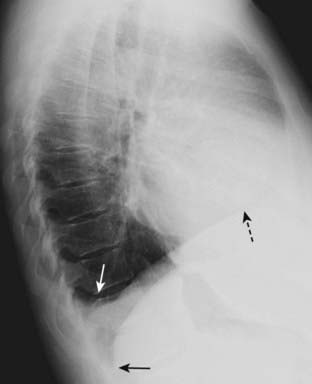

Pleural effusions accumulate in the deep recesses of the costophrenic sulci, filling in their acute angles with the patient upright. This is called blunting of the costophrenic angles (see Chapter 6).

It takes only about 75 cc of fluid (or less) to blunt the posterior costophrenic angle on the lateral film, while it takes about 250-300 cc to blunt the lateral costophrenic angles on the frontal film (Fig. 2-9).

image

Figure 2-9 Blunting of the posterior costophrenic sulcus by a small pleural effusion.

Left lateral view of the chest shows fluid blunting the posterior costophrenic sulcus (solid white arrow). The other posterior costophrenic angle (solid black arrow) is sharp. The pleural effusion is on the right side because the hemidiaphragm involved can be traced anteriorly farther forward (dotted black arrow) than the other hemidiaphragm (the left), which is normally silhouetted by the heart and not visible anteriorly.